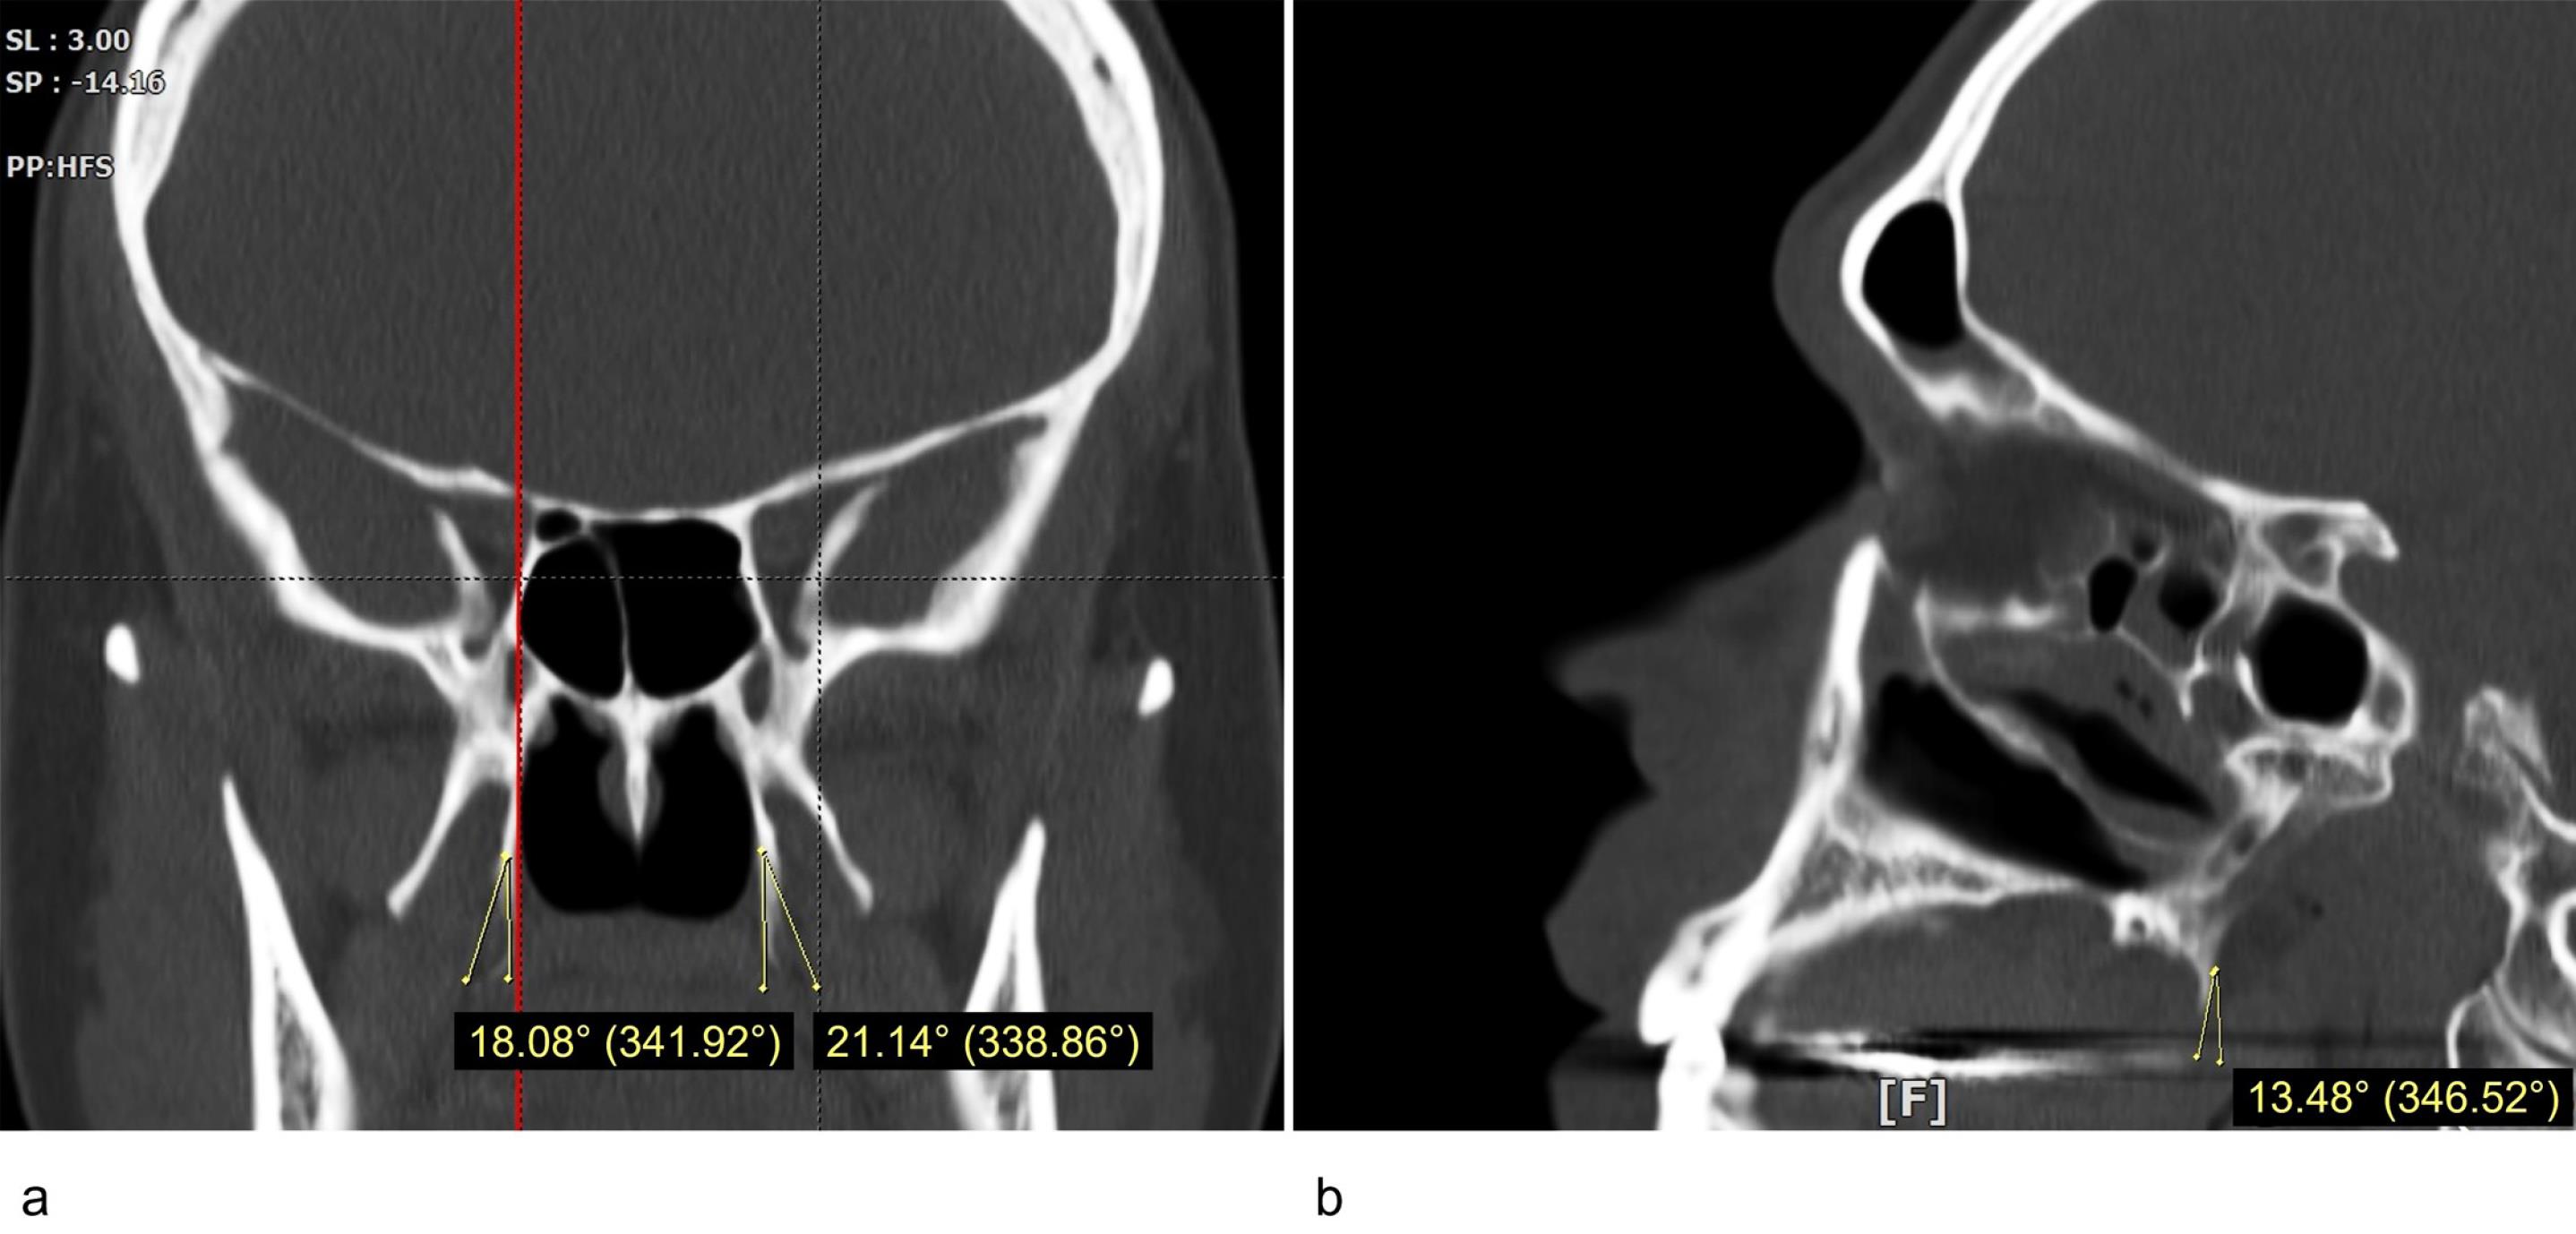

Measurements of the size (length and width) and the inclination of the PH on the coronal and sagittal planes were conducted using the OnDemand 3D Viewer software (available at https://www.ondemand3d.com). The coronal sections were used to measure the length and width of the PH. In order to identify the junctional point between the PH and the pterygoid bone, the Multi-Planar Reformat tool was used to compare the coronal and sagittal views of the same side. The PH length was defined as the longest line connecting the medial pterygoid-PH junction to the tip of the PH. The distance between the most prominent points on the lateral and medial sides of the process was measured as the PH width.9 The coronal inclination of the PH was defined as the mediolateral angle between the PH long axis and the long axis of the medial pterygoid plane. The PH sagittal inclination was defined as the posteroanterior angle between the long axis of the PH and the long axis of the Medial pterygoid plane (Figure 1). The PH morphology was categorized as “Slender” or “Triangle” type according to the study by Nerkar et al.10 Examiner percentage error was calculated by repeating 5% of the measurements after two weeks.

Figure 1.

The inclination of the pterygoid hamulus: (a) coronal plane, (b) sagittal plane